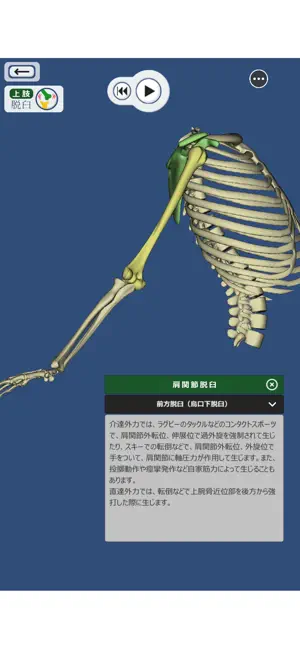

上肢、下肢の骨折と脱臼を3DCGのモデルとアニメーションで再現した骨折と脱臼を学ぶアプリ。

書籍や図譜では分かりにくかった骨折・脱臼の発生機転や転位が立体的に理解できます。

・骨折・脱臼の発生機転をCGアニメーションで再現

・発生機転のワンポイント解説付

- 分かりやすいです このアプリは骨折と脱臼のとても詳しいことが分かるアプリです!それぞれの関節や部位によって項目が分かれてて、自分の調べたい項目をタッチすると名称、説明が書いてあります。1番すごかったのが自分の見たい角度に骨を動かし、その部分で保存できることです。このアプリを使ってたくさん学びたいと思います!